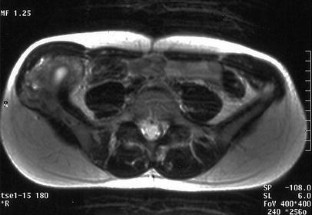

Spontaneous malignant transformation of conventional giant cell tumor (GCT) of bone is exceedingly rare. We report on a case of GCT of the iliac crest in a 35-year-old woman with malignant change into a high-grade osteosarcoma 10 years after the first appearance of GCT on a radiograph. Since the patient refused therapy for personal reasons the tumor remained untreated until sarcomatous transformation occurred. Image cytometry showed DNA aneuploidy and a suspiciously high 2c deviation index (2cDI) in the primary bone lesion. A thorough review of the world literature revealed only seven fully documented cases of secondary malignant GCT which matched the definition of a “sarcomatous growth that occurs at the site of a previously documented benign giant cell tumor” and not treated by radiotherapy. These cases as well as the current one suggest that a spontaneous secondary malignant GCT presents as a frankly sarcomatous tumor in the form of an osteosarcoma or malignant fibrous histiocytoma. It usually appears at sites of typical GCTs—often without any recurrent intermediate state—and is diagnosed 3 or more years after the primary bone lesion. The prognosis is poor.

Fig. 3